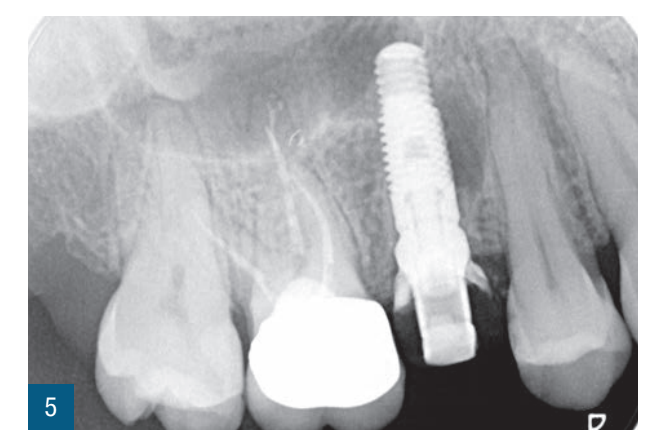

Пацієнтка 36 років звернулася до нас з частковим переломом коронки другого премоляра праворуч (1.5). Після перевірки неможливості консервативного відновлення було заплановано імплантно-протезне лікування з негайною екстракцією для заміни ураженого елемента (Рис. 1,2). Пацієнтка, не курець, була класифікована як ASA 1. Було виконано локалізовану CBCT в ураженій області для перевірки наявності та морфології вестибулярної кісткової стінки навколо елемента, що підлягає екстракції, в альвеолярному відростку. Перед екстракцією 1.5 була виконана цифрова внутрішньоротова відбитка (iTero Flex, Align Technology) зуба та прилеглих ділянок (Рис. 3). Після плескальної анестезії була виконана екстракція, обмежуючи травму пародонтальних тканин, розділяючи корені та використовуючи міні-важелі та синдесмотоми для збереження вестибулярної кісткової пластини. Оцінюючи цілісність альвеоли та сприятливі анатомічні умови, переходять до встановлення імплантату розмірів, що забезпечують адекватну первинну стабільність (4.1 x 11,5 TSVH ZimmerBiomet). Імплантат розміщується в близькій до піднебіння позиції відповідно до вказівок літератури (Рис. 6,7), заповнюючи проміжок між імплантатом та вестибулярною кістковою кортикою за допомогою гетерологічної кісткової пересадки (Copioss Zimmer-Biomet). Монтажний пристрій формують так, ніби це абатмент, і після його закручування на імплантаті проводять сканування. З цифрового внутрішньоротового сканування виконується CAD проектування гвинта загоєння (Рис. 4). У проекті буде використано як передекстраційне сканування, так і сканування з монтажним пристроєм, перетвореним в абатмент, щоб максимально точно відтворити гвинт загоєння. Морфологія гвинта загоєння відтворить існуючі тканинні умови на момент хірургії та дозволить уникнути естетичних дефектів у рожевій естетиці. Завершивши цифрове проектування, виконується 3D-друк з смоли (Lab2 Formlab) кастомізованого гвинта загоєння. Після завершення друку, отриманий гвинт загоєння з смоли Nextdent цементується з авто- та фото-твердим смолистим цементом (Relix Unicem, 3M) до абатмента, отриманого з монтажного пристрою, а потім закручується на імплантат (Рис. 5,6). Було проведено рентгенологічні контролі через три місяці та через рік (Рис. 7,8). Через 3 місяці була виготовлена остаточна коронка через цифровий потік з тим самим сканером та спеціальними сканбоді (Gentek, Zfx), які дозволяють ідентифікувати точне просторове положення імплантату. Через тиждень була передана остаточна монолітна коронка з фарбованої цирконії, закручена на ti-base (Рис. 9,10). Через рік було виконано ще одне сканування для оцінки з часом можливих об'ємних змін періімплантних тканин. Сканування, виконані на етапі передекстракції та через рік, були оброблені за допомогою спеціалізованого програмного забезпечення (meshlab) для оцінки розмірних змін (Рис.11-13).